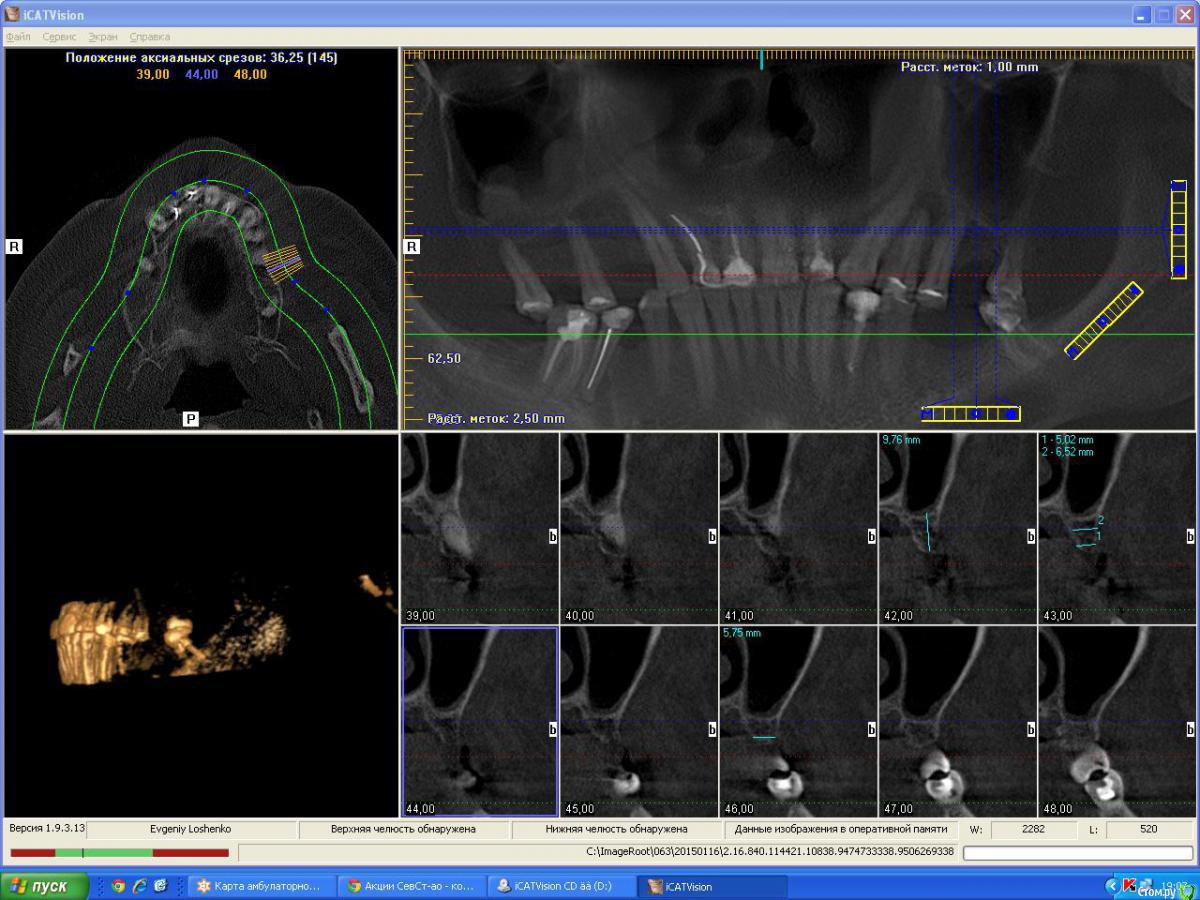

denis1987 Опубликовано 25 февраля, 2015 Поделиться Опубликовано 25 февраля, 2015 Вот такой вот пациент , с адентией в 1 , 2 , 3 и 4 сегментам. Фото прилагаются. Ссылка на комментарий

denis1987 Опубликовано 25 февраля, 2015 Автор Поделиться Опубликовано 25 февраля, 2015 Вот ничего другого на ум не приходит как аугментация костными блоками аутогенными, по крайней мере в 1 и 3 сегментах. Во 2м егменте расщепление + закрытый синус, в 4м вроде как хороший аэродром. Интересует мнение форумчан. Ссылка на комментарий

Aquarius Опубликовано 25 февраля, 2015 Поделиться Опубликовано 25 февраля, 2015 (изменено) Ну в области 14-го ламина точно сработает. И Вы планируете аугментацию на неправильно выставленных срезах!!! Изменено 25 февраля, 2015 пользователем Aquarius Ссылка на комментарий

Aquarius Опубликовано 25 февраля, 2015 Поделиться Опубликовано 25 февраля, 2015 область 26. Срез не захватывает полностью гребень. Не знаю,может я ошибаюсь. Ссылка на комментарий

denis1987 Опубликовано 25 февраля, 2015 Автор Поделиться Опубликовано 25 февраля, 2015 Денис,когда планируете аугментацию? Если не в ближайшие несколько дней, то я постараюсь выложить отпротоколированный кейс с ламиной в области 14. Может что-то возьмете на вооружение. Вроде наконец учёл все ошибки)) И что-то выросло.Все , я понял про что вы говорили в плане среза , на самом деле кусок альвеоляра не влез , настроил норм , но все равно картина не сильно изменилась к сожалению ( Ссылка на комментарий